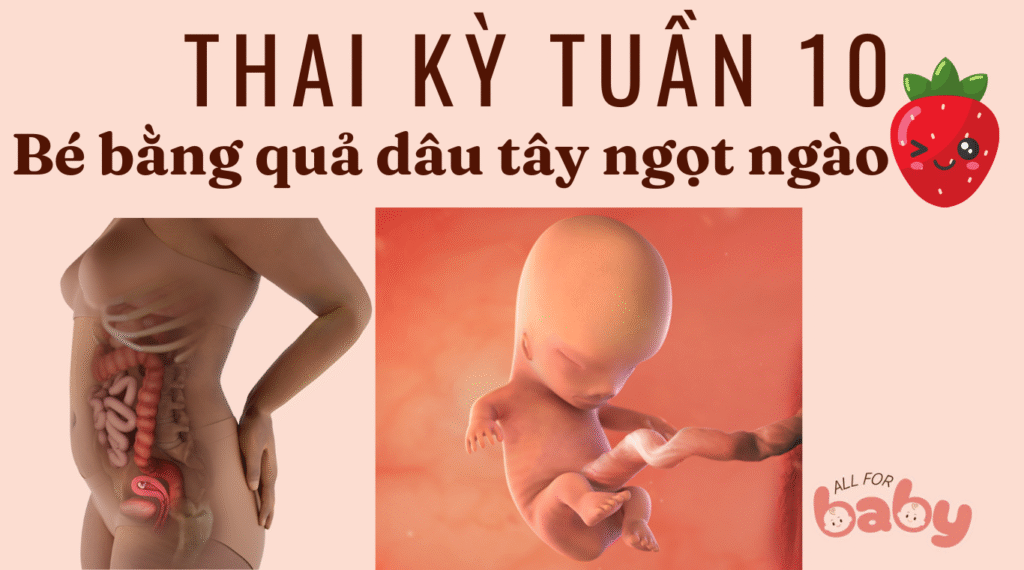

Ở tuần thai thứ 10, bé có chiều dài khoảng 3–4 cm (kích thước bằng một quả dâu tây nhỏ) và nặng khoảng 4–5 gam. Đây là cột mốc đáng nhớ vì:

Bé đã hoàn tất phần lớn những bước phát triển quan trọng của giai đoạn phôi thai, và chính thức được gọi là thai nhi.

Tay, chân, ngón tay và ngón chân đã rõ rệt hơn.

Xương và sụn bắt đầu hình thành, răng sữa cũng đang phát triển bên dưới nướu.

Các cơ quan nội tạng chính như gan, thận, ruột, dạ dày đã bước vào giai đoạn hoạt động.

Bé có thể cử động nhẹ, co duỗi tay chân, dù mẹ chưa cảm nhận được.